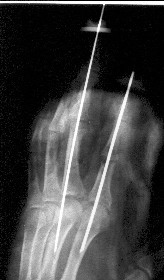

часть пальца висит на кожном лоскуте с латеральной стороны пальца шириной 1 см, повреждены сухожилия сгибателей и разгибателей), многооскольчатым переломом головки основной фаланги 2 пальца, рваной раной в проекции сустава, превышающей половину диаметра пальца (сухожилия целы)(снимок 1, снимок 2). Выполнена ПХО ран, МОС спицами трансартикулярно (снимок 3, снимок 4). При обсуждении тактики лечения возникли разногласия между врачом, выполнявшим ПХО, и заведующим. Зав. отделением считает, что выбранная тактика неверна, и необходимо было после проведения ПХО сделать вытяжение типа Черкес-Заде за пальцы. Просим высказать присутствующих свое мнение о выполненной операции и о дальнейшей тактике лечение больного. Заранее спасибо.

По моему мнению, избранный способ фиксации является правильным.